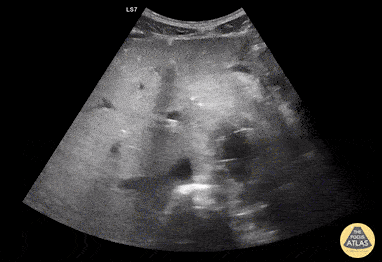

Aortic Endograft Leak - Dr. Lindsay Howe Dr. Tim Scheel Dr. Paul Pelletier - Denver Health

https://www.thepocusatlas.com/aorta